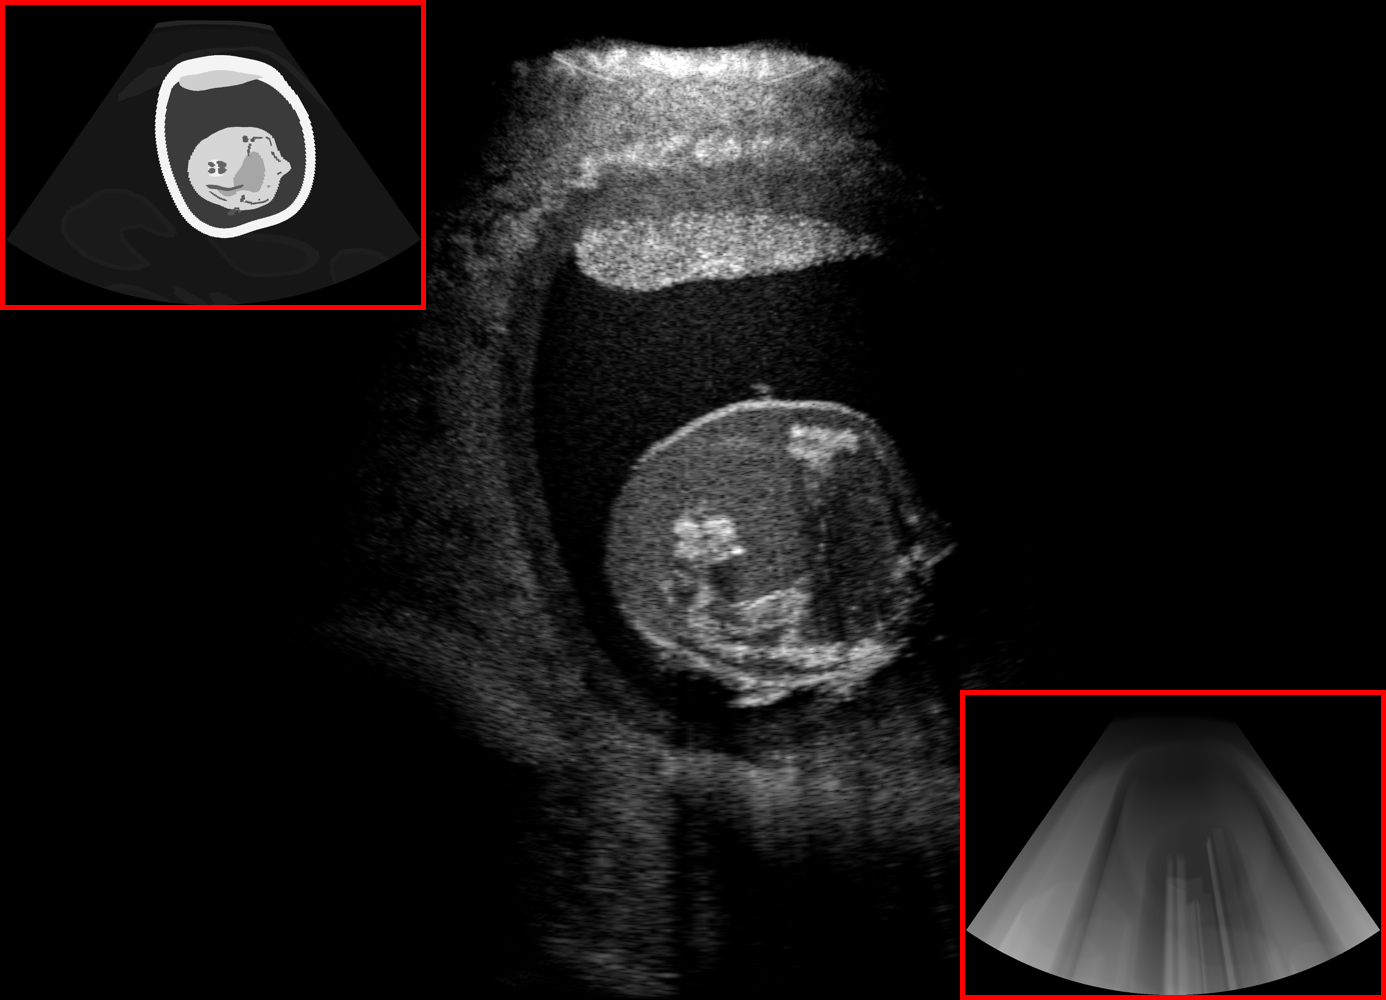

Qualitative evaluation.

Fig. 2 depicts the qualitative results for all the models mentioned above, with arrows pointing at structures relevant to discussion points below. The visual results of the ablated variants of SA2H show substantial quality degradation compared to the full SA2H model, demonstrating the importance of each proposed architectural contribution. Given only segmentation map in the network input, SA2H-att fails to generate acoustic shadows, e.g. those cast by the ribs. Detailed structures such as the cervical vertebrae are blurred out in the SA2H-concat results, which also contain hallucinated structures mainly due to insufficient preservation of input information along the encoding-decoding path. With SA2H-conv, checkerboard artefacts are observed due to the lack of proposed additional stride-1 convolutional layers. SA2H-noise without any explicit noise input is seen to be sub-optimal at generating textural details. The baseline method NSA2H fails to preserve anatomical structures and acoustic shadows in all cases, while the simulated textures also show significant artefacts such as checkerboard patterns. Realism of different simulation aspects may become relevant given different clinical applications and scenarios. For instance, improved structural preservation, e.g. with the hyperechoic bony structures such as the skull and the ribs, of the final model over its ablated variants and NSA2H may prove relevant in fetal head measurements, while the textural improvements facilitating screening fetal organ maturity, e.g. lungs. Compared to the silver-standard model LSA2H with a low-quality rendered image as additional input, SA2H is seen to be on par in structural preservation. Note that shadowing on homogenous regions (e.g. the rib shadowing on the homogenous lung region on the 4th column of Fig. 2) with our proposed method SA2H is represented more faithfully compared to LSA2H, whereas shadows on structurally complex regions (e.g. the skull shadowing around the heart and surrounding tissues on the 3rd column of Fig. 2) are suboptimal with our SA2H. Therefore, one may have to evaluate our method given particular simulation tasks, e.g. its clinical validity for fetal heart exams. However, even with low quality rendered images, LSA2H leads to artificial enhancements of intensities, lack of acoustic shadows, and low-quality textures especially near the probe, for which SA2H yields satisfactory results as illustrated in Fig. 2.

For the interpretation of the local errors, sample spatial p error maps are depicted in Fig. 3 for LSA2H, NSA2H, and SA2H for the middle two examples shown in Fig. 2. Both images generated by NSA2H have a lot of missing structures and accordingly have high error almost all over the map. Artificial skull enhancement with LSA2H is seem to evoke large p error, as shown in the corresponding error map, whereas the bright spots in the error map of SA2H reflect some hallucinated shadows and structure in the brain. All of above mentioned regions of interest are marked by red arrows. In the bottom example, SA2H fails to generate faithful content at the bottom region marked by red circles, which is well indicated by the error map as well.